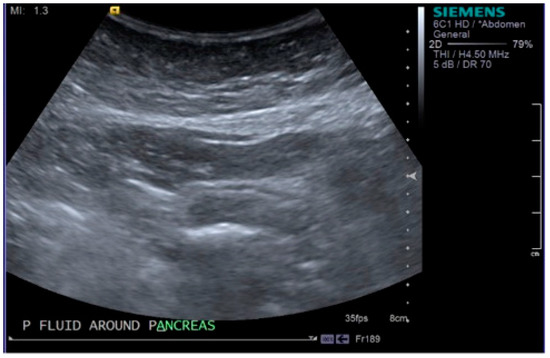

2. Case Report